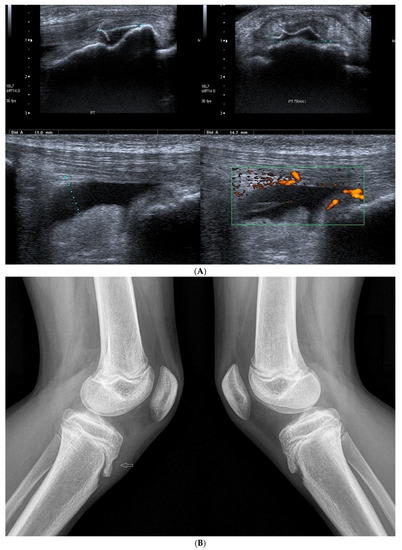

3.2.2. Osgood–Schlatter Disease

3.2.3. Ligament Injuries